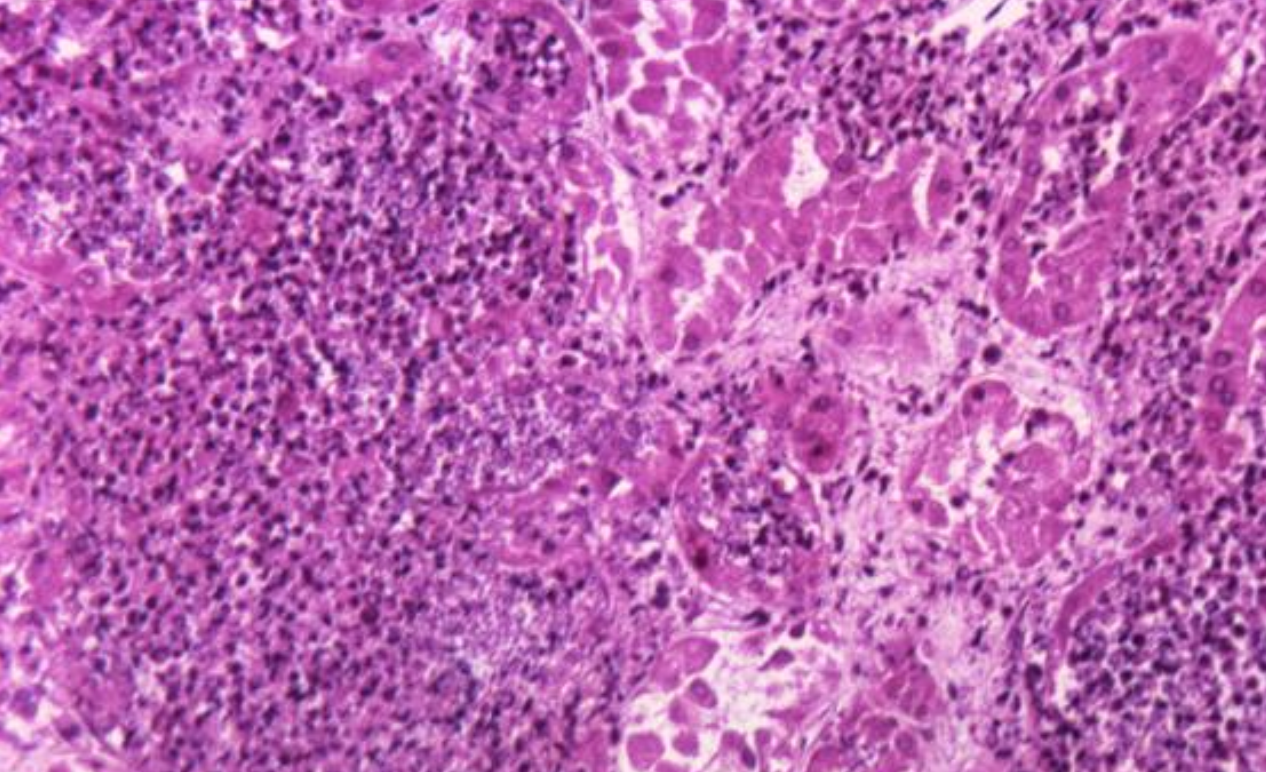

Summary of Recent Updates too Invasive Candidiasis Guidelines

This article details meaningful shifts in the guidelines for diagnosing and treating invasive candidiasis, reflecting a move towards more targeted approaches and a strong emphasis on antifungal stewardship. Here’s a breakdown of the key changes: